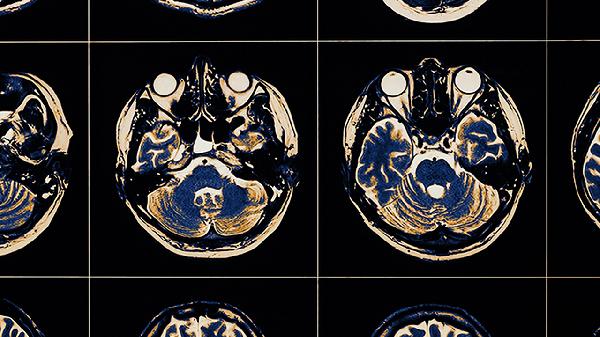

右侧大脑中动脉闭塞怎么治疗

右侧大脑中动脉闭塞可通过药物治疗、血管内治疗、手术治疗、康复治疗、生活干预等方式治疗。右侧大脑中动脉闭塞通常由动脉粥样硬化、心源性栓塞、血管炎性疾病、血液高凝状态、血管畸形等原因引起。